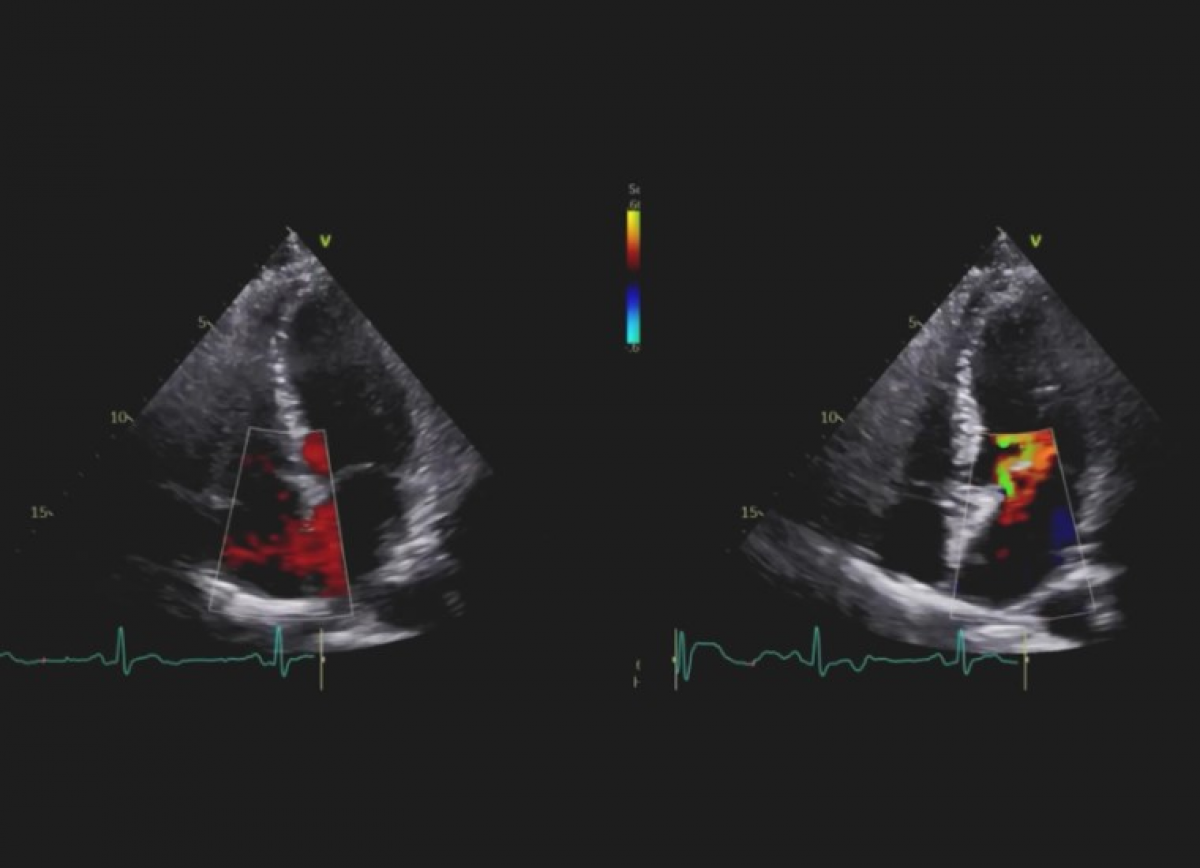

Pacjent ze spoczynkowymi bólami zamostkowymi i gorączką od kilku dni.

Pacjent z niewydolnością serca z obniżoną frakcją wyrzutową.

Zapalenia mięśnia sercowego.

Echokardiografia przezklatkowa.

Ocena funkcji lewej komory.

Ocena odkształcenia podłużnego.